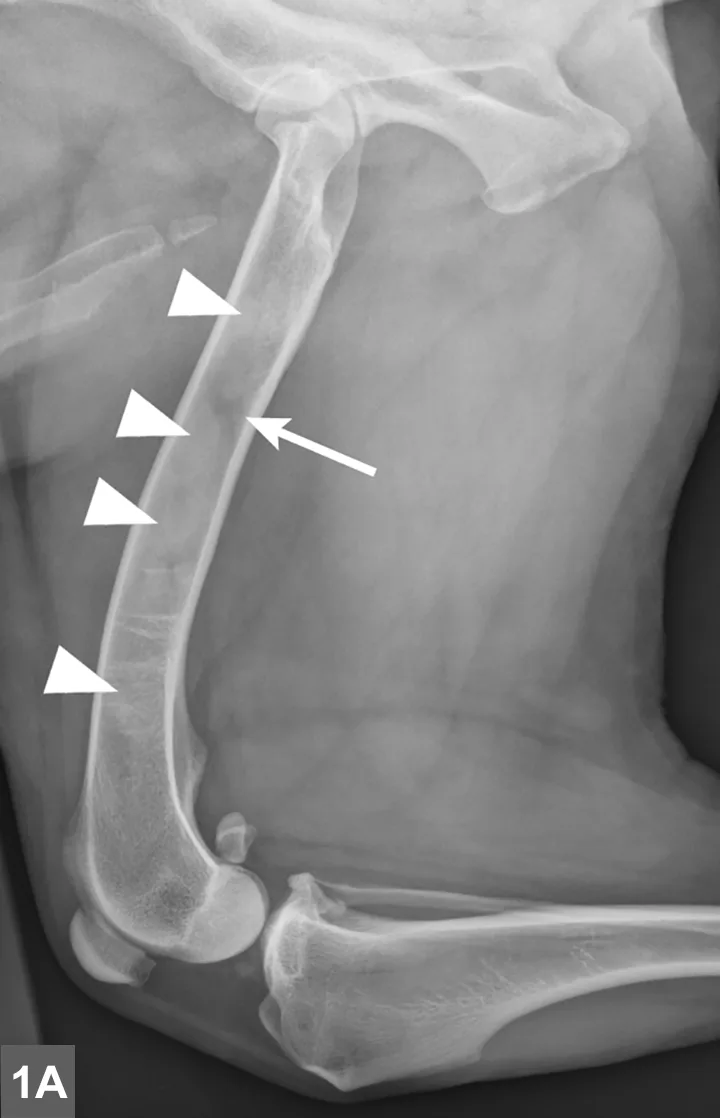

Radiographic signs of panosteitis frequently lag days to weeks behind clinical signs.1,3 The earliest radiographic sign of panosteitis is a decrease in opacity around the nutrient foramen. Later signs include an increase in mineral opacity within the medullary canal of long bones and loss of the normal trabecular bone pattern (Figure 1). Smooth periosteal and endosteal new bone may also be seen in more severe cases (Figure 2). Radiographs of the affected limb may be compared with those of the contralateral limb to assist in diagnosis. Nuclear scintigraphy may assist in diagnosis in cases in which radiographic changes have not yet developed.4

FIGURE 1A

Lateral radiographic projections of the femur (A) and ulna (B, next slide) in dogs with early signs of panosteitis. Note the radiolucency around the nutrient foramen (arrows) and increased opacity within the medullary canal (arrowheads) in both cases.